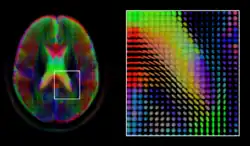

The diffusion tensor,[58] a 3 × 3 symmetric positive-definite matrix, offers a straightforward solution to both of these goals. It is proportional to the covariance matrix of a Normally distributed local diffusion profile and, thus, the dominant eigenvector of this matrix is the principal direction of local diffusion. Due to the simplicity of this model, a maximum likelihood estimate of the diffusion tensor can be found by simply solving a system of linear equations at each location independently. However, as the volume is assumed to contain contiguous tissue fibers, it may be preferable to estimate the volume of diffusion tensors in its entirety by imposing regularity conditions on the underlying field of tensors.[59] Scalar values can be extracted from the diffusion tensor, such as the fractional anisotropy, mean, axial and radial diffusivities, which indirectly measure tissue properties such as the dysmyelination of axonal fibers [60] or the presence of edema.[61] Standard scalar image computing methods, such as registration and segmentation, can be applied directly to volumes of such scalar values. However, to fully exploit the information in the diffusion tensor, these methods have been adapted to account for tensor valued volumes when performing registration [62][63] and segmentation.[64][65]

Given the principal direction of diffusion at each location in the volume, it is possible to estimate the global pathways of diffusion through a process known as tractography.[66] However, due to the relatively low resolution of diffusion MRI, many of these pathways may cross, kiss or fan at a single location. In this situation, the single principal direction of the diffusion tensor is not an appropriate model for the local diffusion distribution. The most common solution to this problem is to estimate multiple directions of local diffusion using more complex models. These include mixtures of diffusion tensors,[67] Q-ball imaging,[68] diffusion spectrum imaging [69] and fiber orientation distribution functions,[70][71] which typically require HARDI acquisition with a large number of gradient directions. As with the diffusion tensor, volumes valued with these complex models require special treatment when applying image computing methods, such as registration[72][73][74] and segmentation.[75]